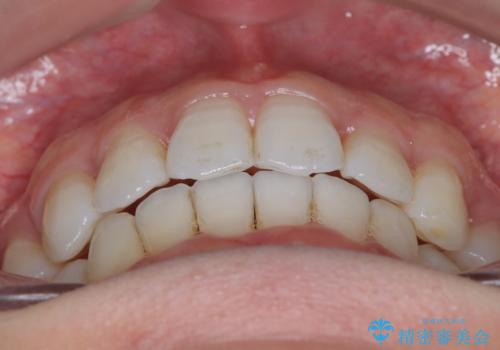

【抜歯インビザ】凸凹を綺麗になおしたい

- 前歯の凸凹を主訴に来院されました。

叢生量が多いため、抜歯が必要となるため、ワイヤー矯正をお勧めしましたが、患者さんの希望によりインビザラインで治療を開始しました。途中でワイヤーリカバリーを必要とせず終了でき患者さんには満足していただけました。